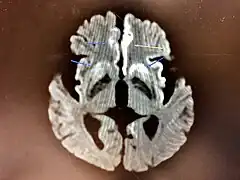

The symptoms of CJD are caused by the progressive death of the brain's nerve cells, which are associated with the build-up of abnormal prion proteins forming in the brain. When brain tissue from a person with CJD is examined under a microscope, many tiny holes can be seen where the nerve cells have died. Parts of the brain may resemble a sponge where the prions were infecting the areas of the brain.[17]

Histopathology

Testing of tissue remains the most definitive way of confirming the diagnosis of CJD, although it must be recognized that even biopsy is not always conclusive.[51]

In one-third of people with sporadic CJD, deposits of "prion protein (scrapie)", PrPSc, can be found in the skeletal muscle and/or the spleen.[52] Diagnosis of vCJD can be supported by biopsy of the tonsils, which harbor significant amounts of PrPSc; however, biopsy of brain tissue is the definitive diagnostic test for all other forms of prion disease. Due to its invasiveness, biopsy will not be done if clinical suspicion is sufficiently high or low. A negative biopsy does not rule out CJD, since it may predominate in a specific part of the brain.[53]

The classic histologic appearance is spongiform change in the gray matter: the presence of many round vacuoles from one to 50 micrometers in the neuropil, in all six cortical layers in the cerebral cortex or with diffuse involvement of the cerebellar molecular layer.[54] These vacuoles appear glassy or eosinophilic and may coalesce. Neuronal loss and gliosis are also seen.[55] Plaques of amyloid-like material can be seen in the neocortex in some cases of CJD.[56]

However, extra-neuronal vacuolization can also be seen in other disease states. Diffuse cortical vacuolization occurs in Alzheimer's disease, and superficial cortical vacuolization occurs in ischemia and frontotemporal dementia. These vacuoles appear clear and punched-out. Larger vacuoles encircling neurons, vessels, and glia are a possible processing artifact.[53]